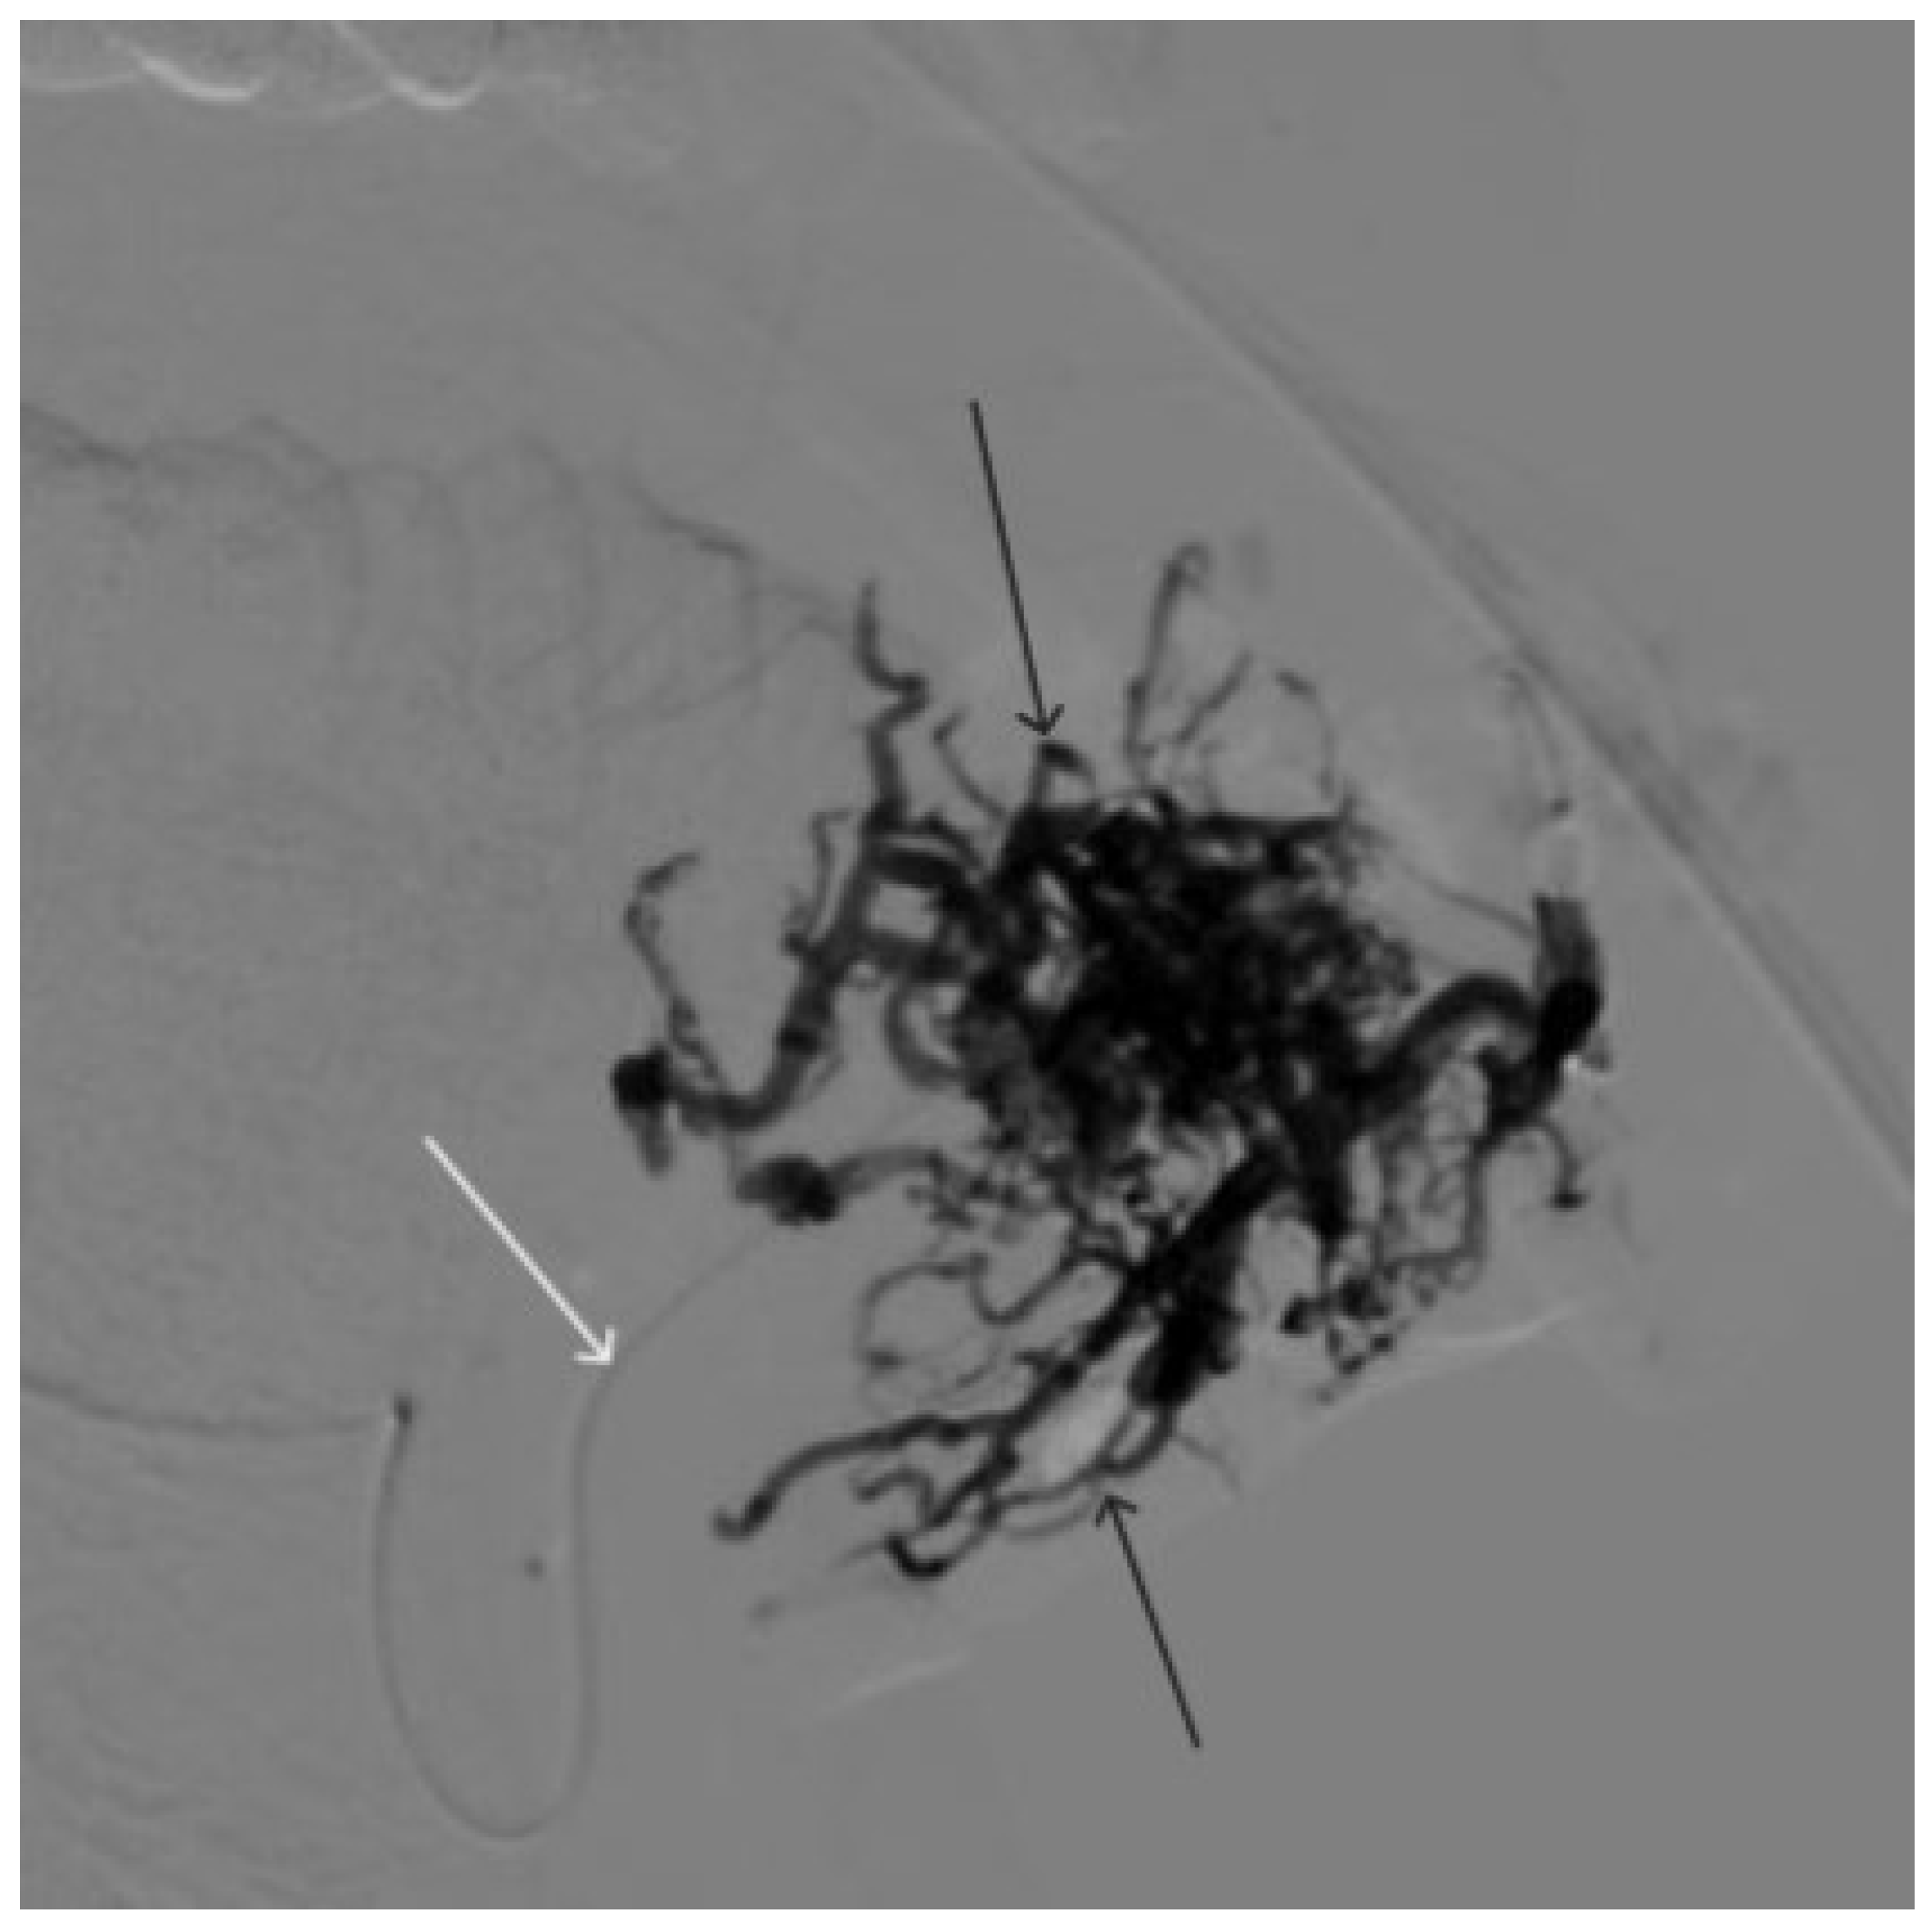

A 58-year-old male patient was admitted to the clinic complaining of a palpable formation in the left submandibular region. When angiography was performed, the filling of the vascular network of the tumor of the left submandibular region from the branches of the left occipital artery, as well as the muscular branches of the left vertebral artery, was noted (Figure 11). The patient underwent intravascular embolization of the paraganglioma with 7.5 mL of non-adhesive composition ONYX18 (Figure 12 and Figure 13). The vascular network supplying the paraganglioma was partially switched off (Figure 14). There were no complications. The mRs score at discharge was 1.

Figure 12. Distribution of ONYX18 along the vascular network of the paraganglioma: (a) direct projection, (b) lateral projection (white arrows indicate filling of the vascular network of the paraganglioma, black arrows indicate an inflated balloon in the left internal carotid artery).

Figure 13. X-ray in single shot mode. (ac) Demonstration of gradual spreading of ONYX18 (NAGLEMs cast) through the vascular network of the paraganglioma direct projections (black arrows indicate filling of the vascular network of the paraganglioma, white arrows indicate an inflated balloon in the left internal carotid artery).